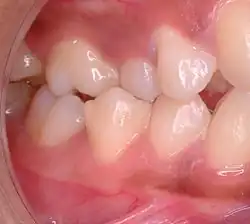

| Malocclusion in 10-year-old girl | |